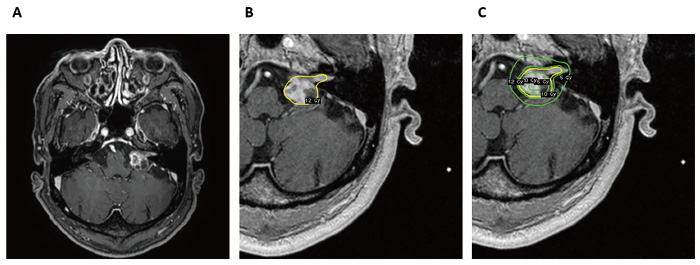

A 73-year-old man presented with left-sided sudden sensorineural hearing loss in 2015 (Fig. 1, timeline figure). The patient underwent magnetic resonance imaging (MRI), which revealed a mass lesion with a maximum diameter of 20 mm in the left cerebellopontine angle (CPA) (Fig. 2A). The patient was diagnosed with Koos grade 3 vestibular schwannoma and underwent GKS in 2016. The prescribed peripheral dose was 12 Gray (Gy) at a 53% isodose line, with a 96% coverage (Fig. 2B, C). The initial tumor volume was 3.260 cc. His hearing status was improved before GKS.

Fig. 2

Fig. 2 A: Initial axial T1-weighted post-contrast MRI showing a left vestibular schwannoma with tumor volume of 3.260 cc. B, C: The tumor was treated with GKS with a prescribed peripheral dose of 12 Gray (Gy), 53% isodose line, and covering 96%. The yellow line indicates the 12 Gy isodose curve and the green lines indicate the 5 Gy, 10 Gy and 15 Gy from the outside to the inside, respectively.